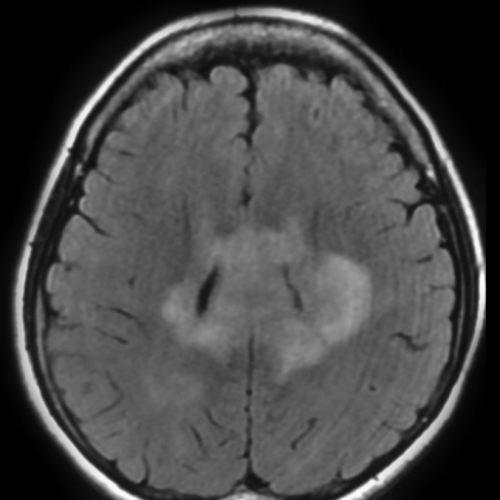

Caso clinico 3

Uomo di 55 anni con cefalea e deficit cognitivo lieve. RM encefalo mostra una lesione periventricolare iperintensa in FLAIR e bilaterale. Viene iniziata terapia steroidea empirica → dopo 10 giorni la lesione si riduce drasticamente.

Qual è il meccanismo che spiega la drastica riduzione della lesione dopo terapia steroidea?

- Riduzione dell’edema vasogenico per stabilizzazione della barriera emato-encefalica

- Citotossicità diretta sugli oligodendrociti

- Apoptosi delle cellule tumorali linfomatose steroido-sensibili

- Riduzione della pressione intracranica

- Vasocostrizione arteriosa

Risposta corretta: C

COMMENTO

Questo è un classico (e pericoloso) scenario di linfoma primitivo del SNC.

Gli steroidi:

- inducono apoptosi dei linfociti neoplastici

- possono far “sparire” la lesione alla RM

Insight radiologico-clinico:

- lesione periventricolare + enhancement omogeneo + restrizione diffusiva

- forte sospetto di linfoma

Trappola:

- dare steroidi prima della biopsia può rendere la diagnosi impossibile

Questo è uno dei pochi tumori che regredisce rapidamente senza essere realmente curato.